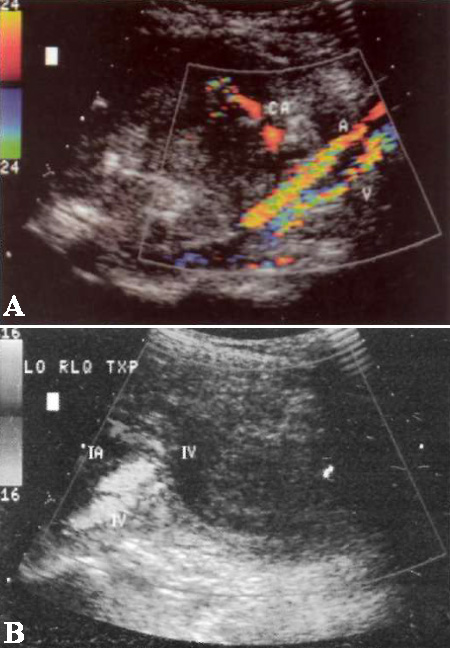

Одновременная пересадка поджелудочной железы и почки демонстрирует показатель выживаемости в течение первого года около 95%, функционирования трансплантата – 85%. Развитие сосудистого тромбоза отмечается в 12% случаев: артериального тромбоза – в 5%, венозного – в 7% случаев соответственно (фото 16).

Фото 16. Венозный тромбоз трансплантата поджелудочной железы. А – поперечное изображение и В – продольное изображение цветовой допплерограммы чревной артерии и прилежащих к ней подвздошной артерии (IA) и вены (IV). Отмечается отсутствие кровотока в анэхогенной вене (V) трансплантата поджелудочной железы

Артериальный тромбоз диагностируют на основании отсутствия в трансплантате артериального кровотока; венозный тромбоз – на основании данных спектральной допплерографии: обратный венозный поток, отсутствие потока в портальном анастомозе. В большинстве случаев тромбируется дистальная треть селезеночной вены, поскольку ее перевязывают и кровь из селезенки не дренирует.